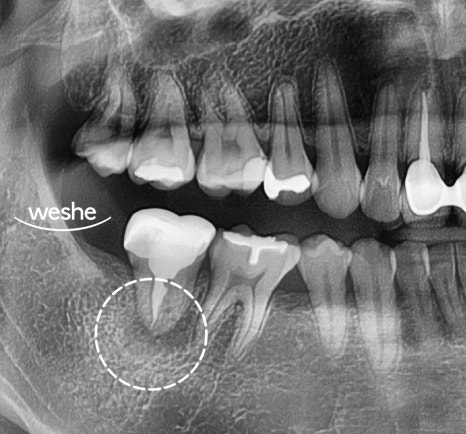

마곡 치과 에서

오른쪽 아래 어금니 부위인

하악 제2대구치를 확인해 보면,

이미 신경 치료가 되어 있고

뿌리(치근) 끝 부위에 염증 소견이 관찰됩니다.

이때 CT 촬영을 통해

치근단 부위를 제외한 주변의 치조골 상태를

정밀하게 확인합니다.

만일 치조골이 양호하다면

치아 재식술을 고려할 수 있는

조건이 됩니다.

특히,

자연치와 주요 조직에 훼손 없이

이를 빼낸 수 있는지,

잔존 치주 인대와 뼈가

건강한지를 평가하는 것이 중요합니다.